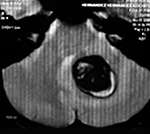

EJEMPLO DE CASO CLÍNICO (8)

Paciente femenino de 29 años de edad con historial de cefalea crónica que presenta súbitamente disdiadococinesia y dismetría izquierda.

El estudio de RMN presenta una lesión bien circunscrita en hemisferio cerebeloso izquierdo con periferia de predominio hiperintenso en T1 y T2, y centro hipointenso, edema perilesional mínimo, así como una imagen de un vaso venoso alimentador que recorre hacia el ángulo pontocerebeloso izquierdo.

Se realizó una craniectomía suboccipital paramedial derecha, así como un abordaje transcortical en el hemisferio cerebeloso izquierdo llegando a la región perilesional de aspecto amarillento, posteriormente se observa una lesión oscuro-verdoso de contenido hemático antiguo, retirando la cápsula y su contenido en la totalidad.

La evolución clínica de la paciente fue satisfactoria solo preservando la dismetría como secuela.

El resultado histopatológico fue consistente en angioma cavernoso.